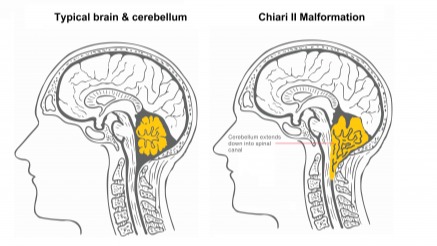

Jackson was born with a rare genetic disorder called Wiedemann–Steiner Syndrome, which he was diagnosed with four years ago. Along with that diagnosis came many serious medical challenges, including severe scoliosis, bone abnormalities, fused vertebrae in his neck, sleep apnea, and most critically, a complex Chiari malformation. This means part of his brain is being pushed down through the base of his skull, leaving very little room for his brain and causing dangerous compression of his brainstem.